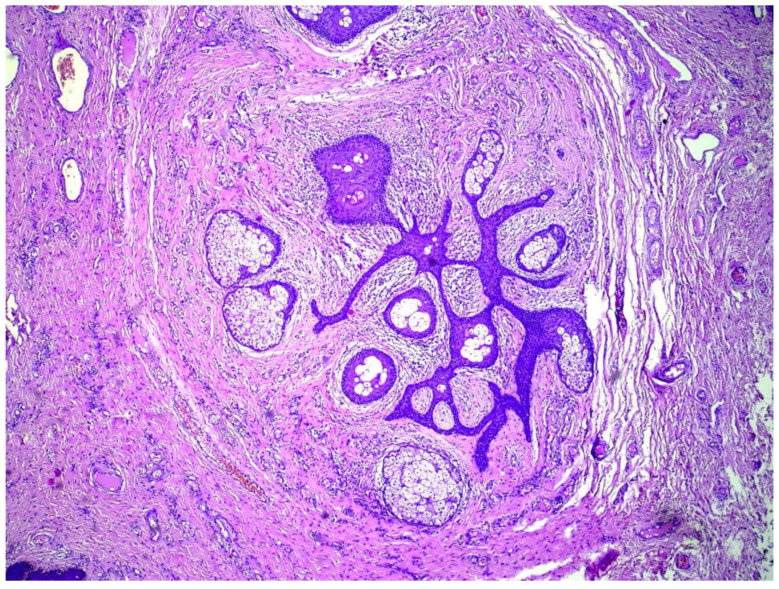

卵泡皮脂腺囊性错构瘤(FSCH)是一种罕见的错构瘤,通常表现为成人面部中央区域的无症状,孤立的圆顶状或带梗丘疹。我们报告一个35岁的女性谁提出了6个月的历史皮肤病变在她的大阴唇。组织学表现包括囊状扩张的毛囊,具有分支状上皮链和相互连接的皮脂腺,与FSCH的诊断一致。FSCH的生殖器变异在1998年首次被描述,从那时起,文献中只报道了6例。我们的目标是提高对这种罕见表现的认识,因为它具有重要的心理意义和误诊的风险。

Folliculosebaceous cystic hamartoma (FSCH) is an uncommon hamartoma that usually presents on the central face area of adults as an asymptomatic, solitary dome-shaped or pedunculated papule. We report a case of a 35-year-old female who presented with six-months history of skin lesions on her labia majora. Histological findings included cystically dilated hair follicles with branching epithelial strands and interconnecting sebaceous gland consistent with the diagnosis of FSCH. The genital variant of FSCH was first described in 1998 and since then only six cases have been reported in the literature. We aim to increase awareness of this rare presentation due to the significant psychological implications and the risk of misdiagnosis.